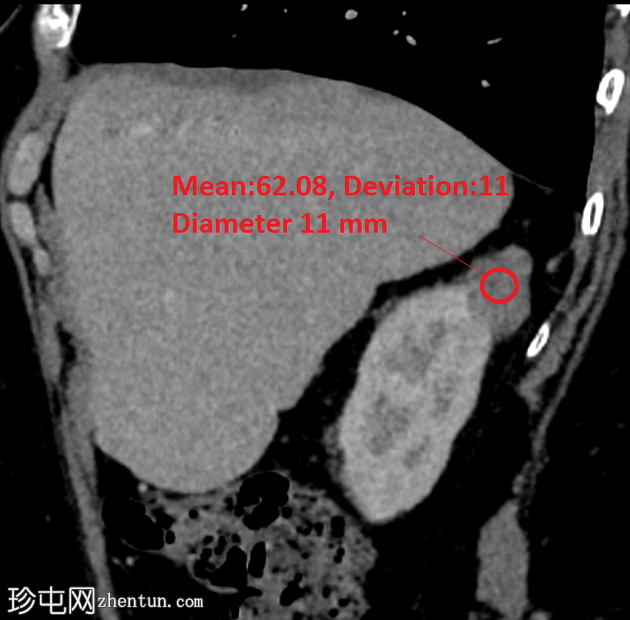

轴位

平扫

右肾后上极可见2.8 cm外生性强化病灶,提示肾细胞癌(RCC)。右肾静脉和下腔静脉通畅。未见明显局部淋巴结肿大。右肝叶可见高密度金属影。可见含脂肪的脐疝。